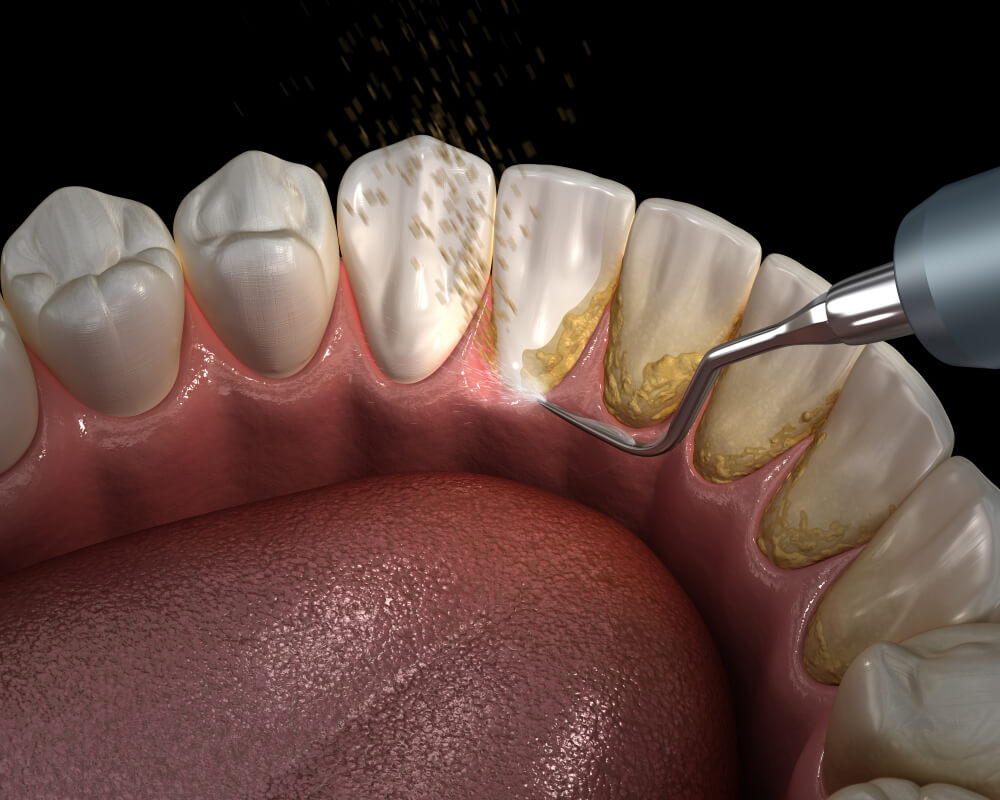

Ukoliko se ne održava dobra oralna higijena, koja uključuje upotrebu ne samo klasične, već i interdentalne četkice, zubni plak se kalcifikuje i pretvara u kamenac. Kako je on jedan od vodećih uzročnika za najčešće bolesti desni, njegovo uklanjanje je neophodno radi očuvanja celokupnog zdravlja.

Peskiranje zuba predstavlja stomatološki tretman detaljnog čišćenja zuba. Vrši se u slučaju kada uklanjanje zubnog kamenca nije u potpunosti otklonilo sve pigmentacije na zubima.

Specijalni aparat, koji se naziva peskir, izbacuje pod pritiskom mešavinu vode i abrazivnih čestica. Upravo ove čestice, koje su zapravo natrijum bikarbonat, deluju na površinu zuba uklanjajući mrlje. Takođe, otklanjanju pigmente sa nepristupačnih delova između dva susedna zuba.

S obzirom da se u ovom prostoru često zadržavaju bakterije, peskiranjem se smanjuje rizik od upala desni, a samim tim i od opasnog oboljenja – parodontopatije.

Čitava procedura je potpuno bezbolna i neškodljiva za zube. Za dodatnu prijatnost često se koriste voćne arome. Peskirom se tretiraju velike površine odjednom, te tretman traje oko 20 minuta.